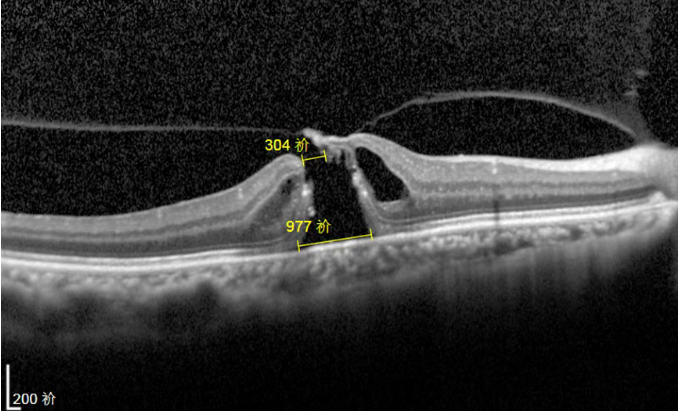

眼底病专家、爱尔眼科医院鄂豫区副总院长李玉军,通过OCT(光学相干断层扫描)等检查结果,发现王女士右眼黄斑出现了较大的全层裂孔。

其眼底OCT(光学相干断层扫描)显示,她右眼的黄斑裂孔已经完全闭合。